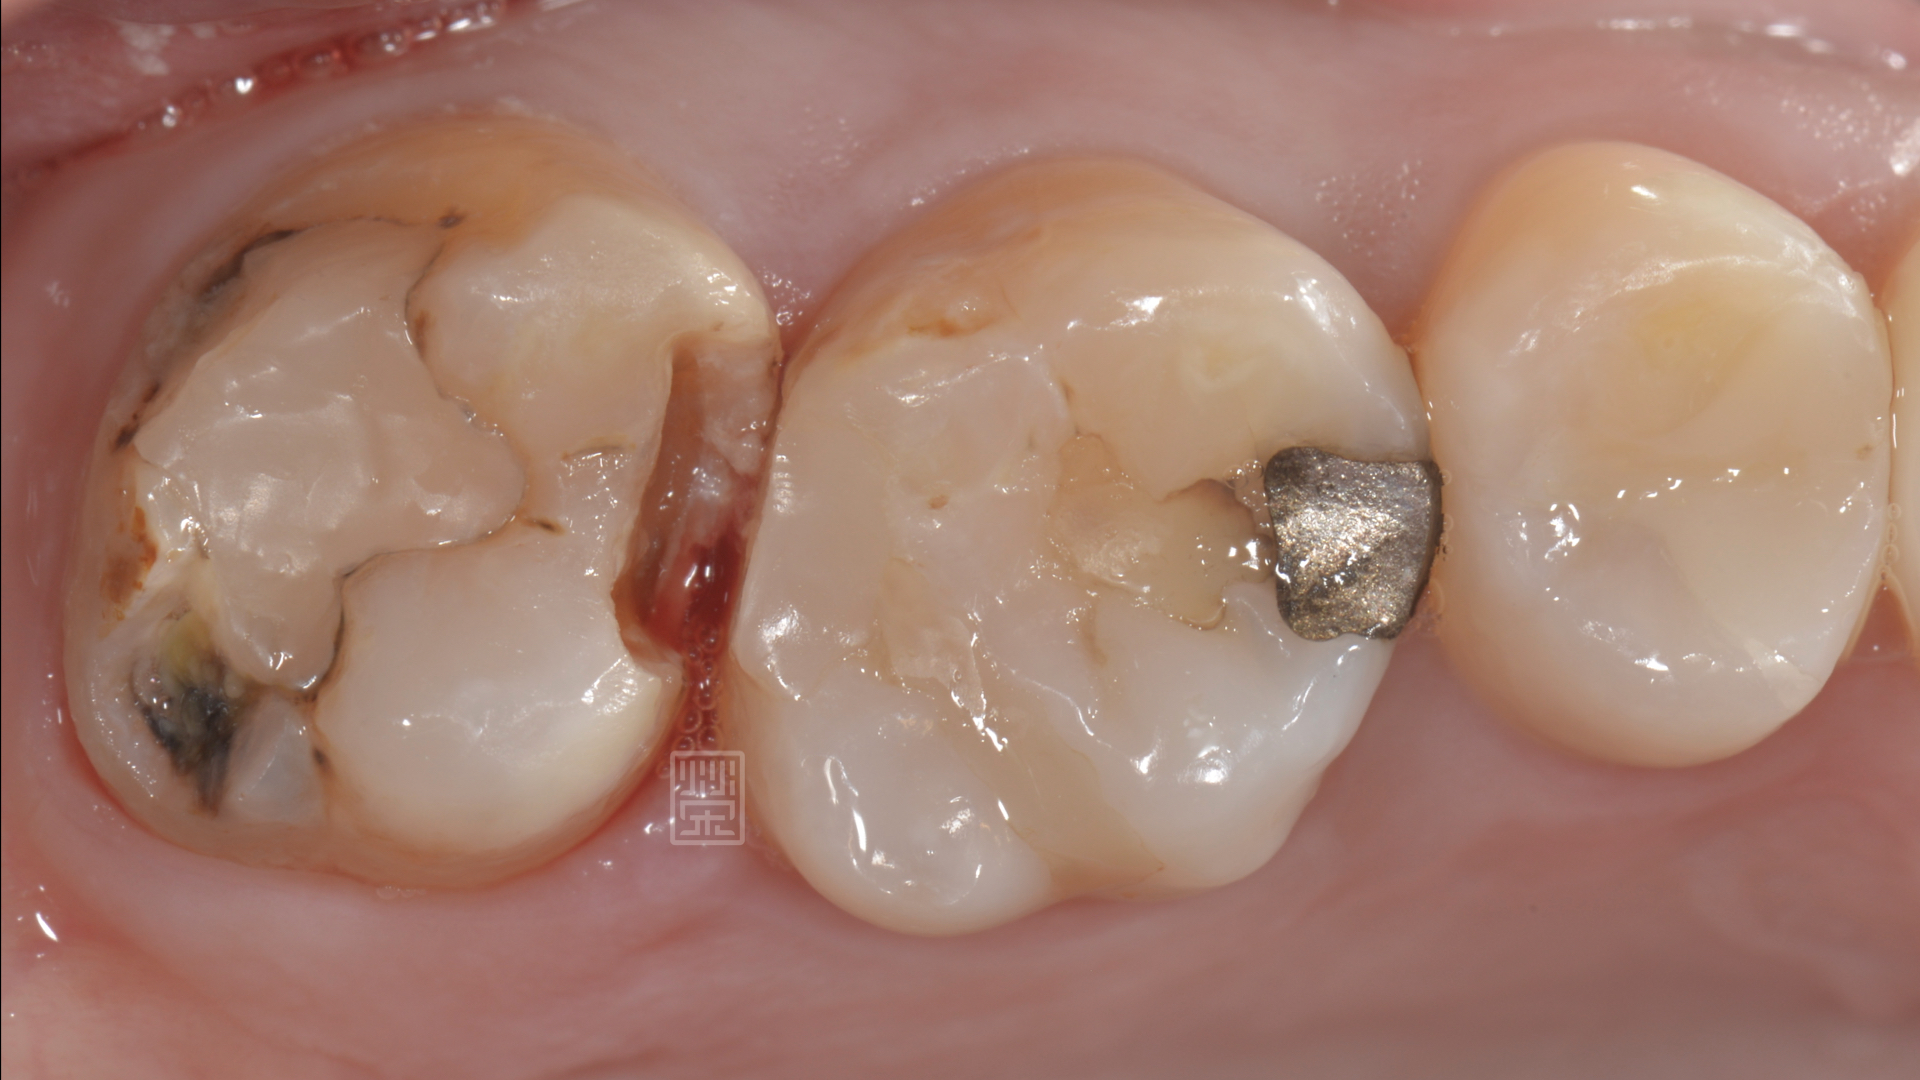

陳小姐某天吃東西,突然發現好像咬到硬硬的,但仔細一看,似乎不是食物,而是自己的牙齒!!!而且牙齒就空了一個洞,緊張之餘,馬上安排門診檢查。

經由診斷後,應該是蛀牙造成牙齒損傷,咬到硬物,牙齒斷裂,幸運的是,牙齒神經依然健康,只是牙齒齒質受損嚴重,

牙齒破裂

頰側大蛀牙